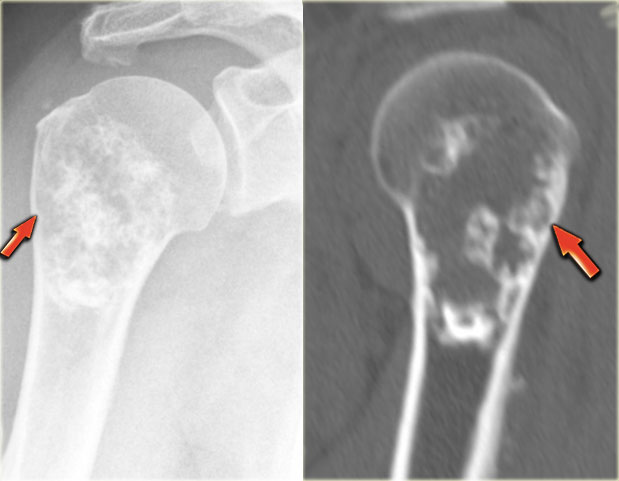

Chondroblastoma (4)

Here a lesion located in the epi- and metaphysis of the proximal humerus.

The lesion is predominantly calcified.

Coronal T1W image shows lobulated margins and peripheral low SI due to the calcifications.

Notice the surrounding decreased signal intensity of the bone marrow, consistent with edema.

Edema almost always accompanies chondroblastoma, but is unusual in other chondroid tumors, like enchondroma or low-grade chondrosarcoma.

Diagnosis: Chondroblastoma.

On the left an eccentric well-defined lytic lesion in the proximal femur.

CT image shows a lobulated and sclerotic border.

The location in the epiphysis is typical for a chondroblastoma.

Continue with the MR.

Same patient.

Coronal T2-WI with FS demonstrates high SI of the lesion with a low intensity sclerotic border with perilesional edema.